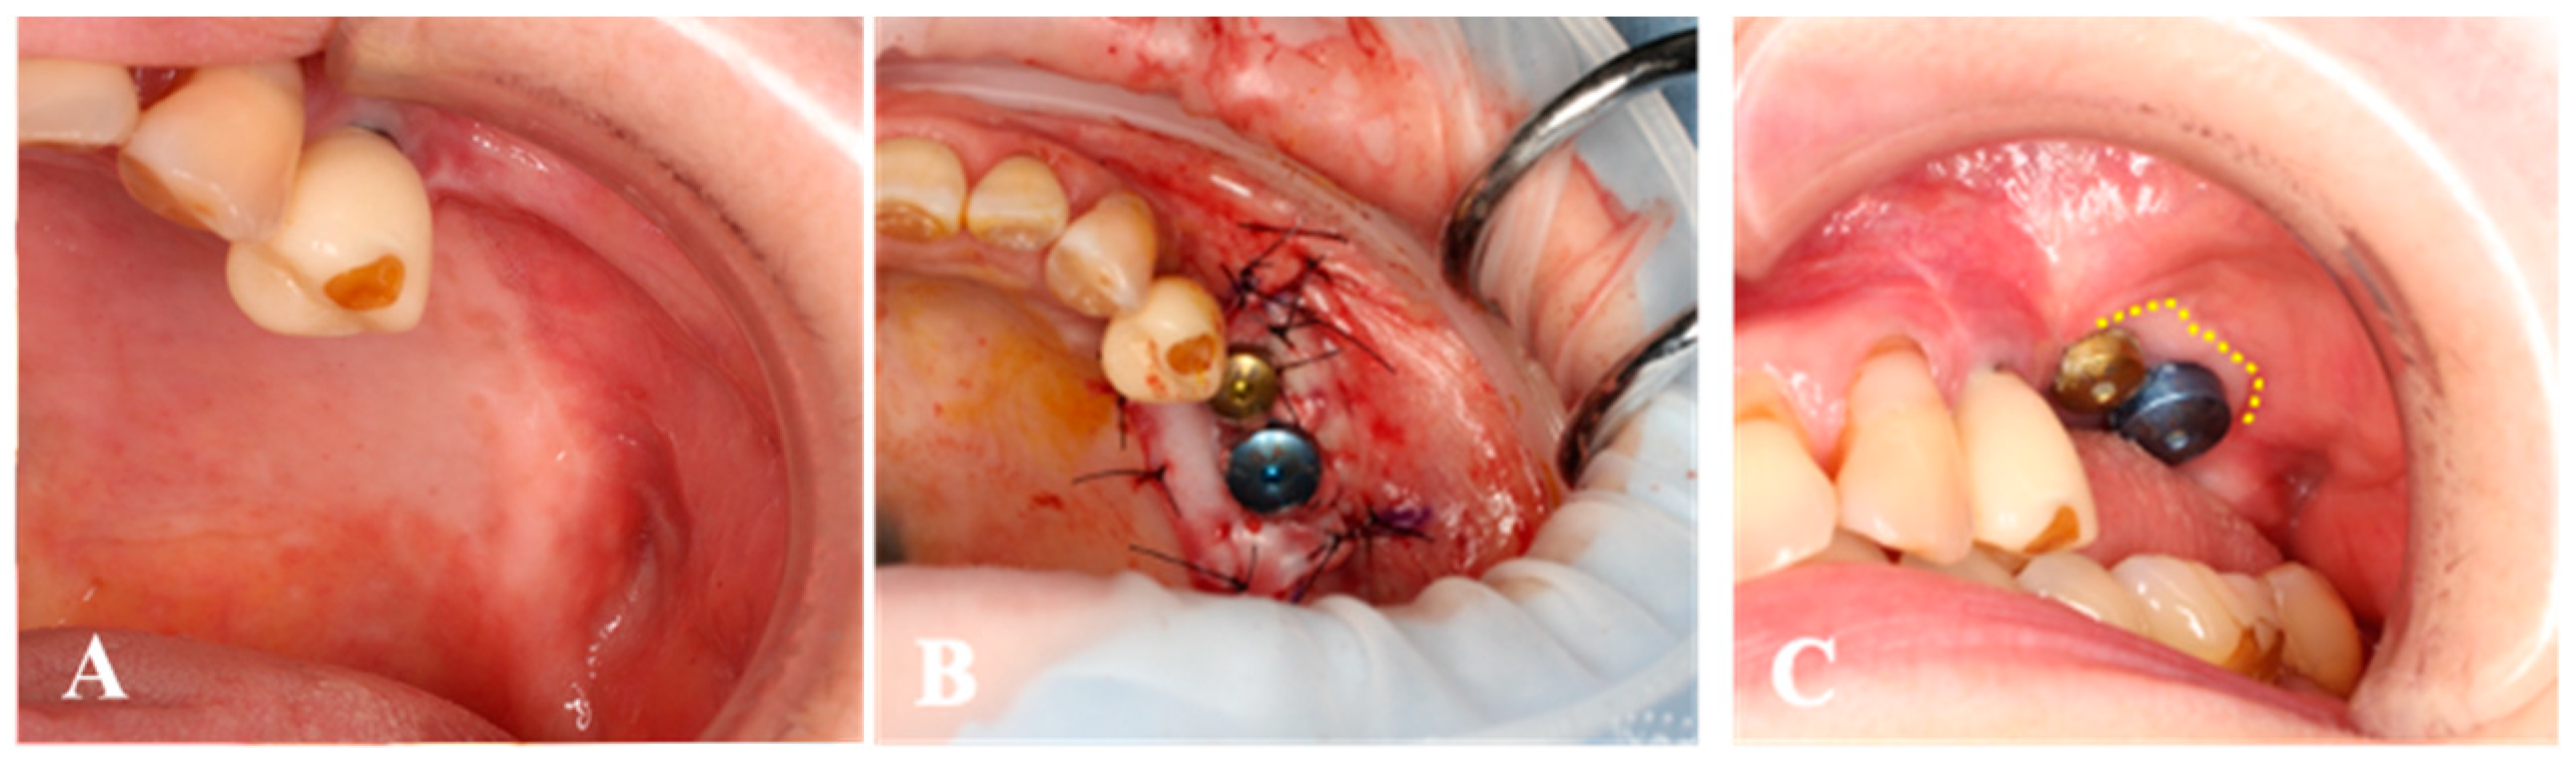

Case 3. A 71-year-old woman who had the implants placed on 25 and 26 was submitted to second-stage surgery at 6 months post-first surgery (Figure 6). There was little keratinized tissue band in the left maxillary premolar region. The non-keratinized tissue band was shifted to both buccal and palatal sides with split-thickness. From the palatal mucosa of the left maxillary tuberosity, the gingival connective tissue was harvested, and a collagen sheet (size 20 × 20 mm2) was seated around the healing abutments. Four weeks after surgery, the peri-implant mucosa was obviously increased surrounding the healing abutment. Throughout the whole period, no AEs were observed.

Figure 6.

Case 3. (A); The keratinized tissue band is almost disappeared. (B); Non-keratinized tissue band is shifted both buccal and palatal sides with split-thickness. The collagen sheet with micronized-gingiva is seated around the healing abutments. (C); The peri-implant mucosa is found surrounding the healing abutment (dotted-line) 4 weeks after surgery.